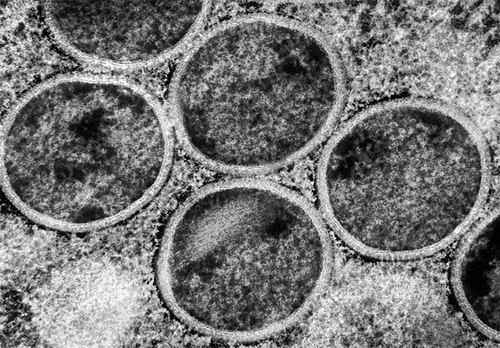

猴痘病毒似乎更容易在人与人之间传播。图片来源:NIAID/SPL